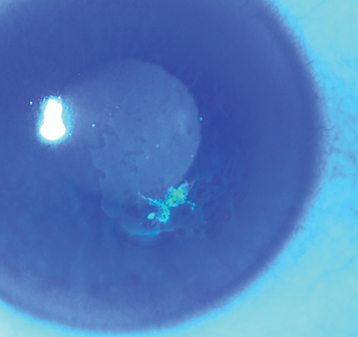

Figure 4.2.1: Resolving epithelial defect with paracentral area of negative fluorescein staining in recurrent corneal erosion.

Localized irregularity with loose corneal epithelium (fluorescein dye may outline the area with negative or positive staining) or a corneal abrasion (see Figure 4.2.1). Epithelial changes may resolve within hours of the onset of symptoms so abnormalities may be subtle or absent when the patient is examined.